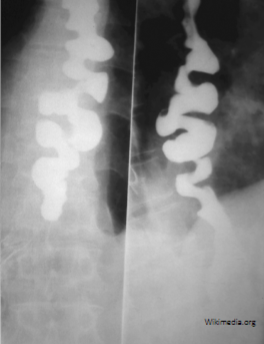

Beak sign on Barium swallow with mega-esophagus

Achalasia